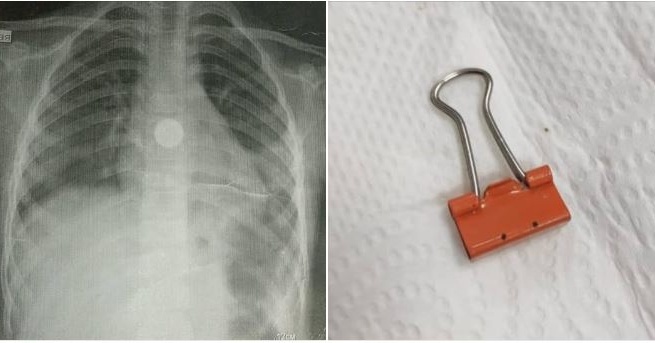

Улуттук эне жана баланы коргоо борборуна инородный телолору менен эки бала келип түштү. Дарыгерлердин ыкчам аракетинин аркасында, кыздардын абалы туруктуу. Ата-энелерге балдардын коопсуздугуна көңүл буруу эскертилди. 🔍 Улуттук эне жана баланы коргоо борборуна эки бала чет өлкөлүк денелер менен келип түшкөн. 👧 Биринчи учур: кыз кагаз кысгычты кокусунан жутуп жиберген, бирок эндоскопиялык кийлигишүү аркылуу ийгиликтүү чыгарылды. 🩺 Экинчи учур: 2018-жылы туулган кыздын дем алуу жолдоруна чет өлкөлүк дене тыгылып калган, бирок дарыгерлер аны тез арада чыгарып, абалын туруктуу кылышты. 👨‍👩‍👧‍👦 Дарыгерлер ата-энелерге балдардын ойноп жаткан нерселерин жана алардын жүрүм-турумун тыкыр көзөмөлдөөнү эскертишет. ⚠️ Чет өлкөлүк денелердин дем алуу жана тамак сиңирүү органдарына кириши өмүргө коркунуч туудурушу мүмкүн.

👧 Биринчи учур: кыз кагаз кысгычты кокусунан жутуп жиберген, бирок эндоскопиялык кийлигишүү аркылуу ийгиликтүү чыгарылды.

🩺 Экинчи учур: 2018-жылы туулган кыздын дем алуу жолдоруна чет өлкөлүк дене тыгылып калган, бирок дарыгерлер аны тез арада чыгарып, абалын туруктуу кылышты.